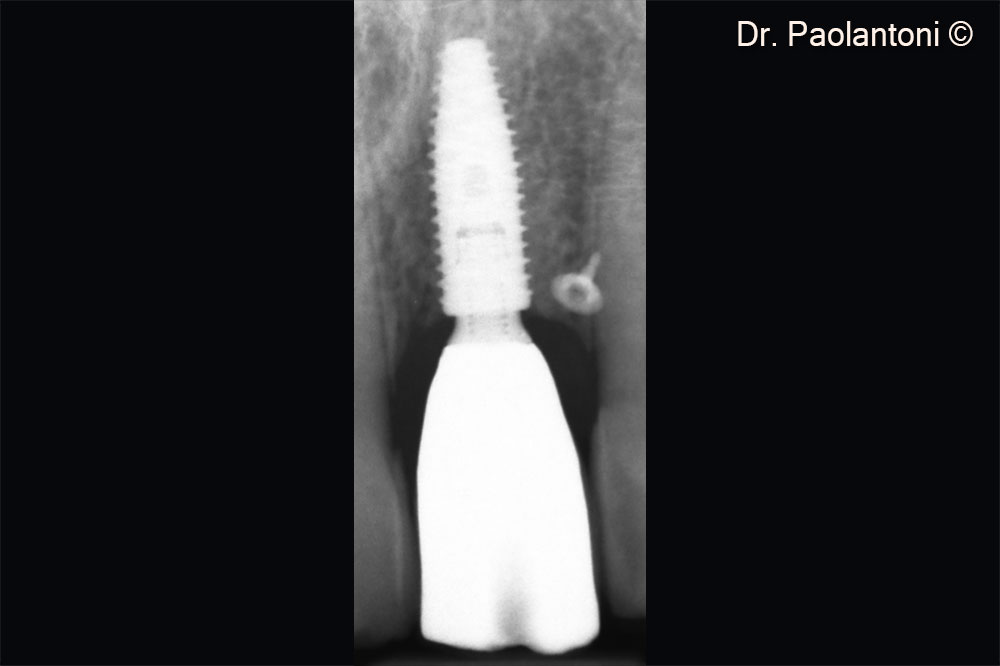

Rx control